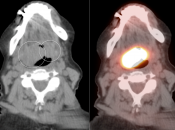

Symmetric, Bilateral Tonsillar Uptake:

The palatine tonsils frequently demonstrate significant metabolic activity.

Bilateral and fairly symmetric FDG-uptake in non-enlarged palatine tonsils is typically a normal finding, and is usually not mentioned in a report.

Bilateral and fairly symmetric FDG-uptake in enlarged palatine tonsils is nearly always inflammatory in nature (although can be seen with lymphoma).

Unilateral FDG-Avid Tonsil (or Relative Increased Avidity of One Tonsil):

Special care is required when assessing the incidental finding of a unilateral hot tonsil (or relative increased uptake within one tonsil) — even though most unilateral hot tonsils are benign. Proposed techniques for assessment have included SUV threshold cutoff values, metabolic tumor volume assessment, and SUV ratios.

Unfortunately, it is advisable to raise at least a degree of concern for most FDG-avid unilateral tonsillar findings. The level of suspicion, of course, depends on the presentation.